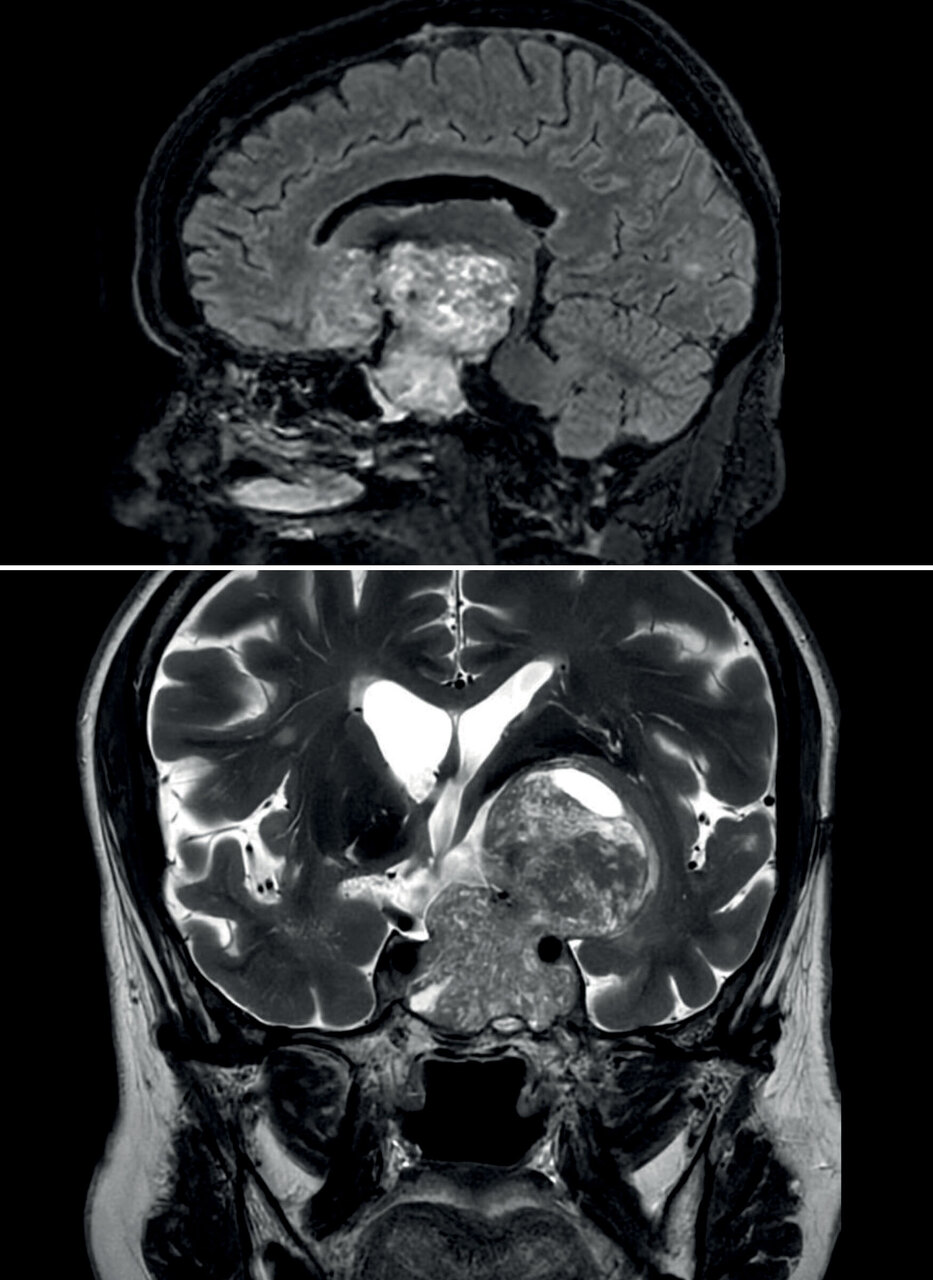

Une femme âgée de 66 ans est hospitalisée en raison de céphalées et d’une hémianopsie bitemporale. Une imagerie par résonance magnétique est réalisée.

L’IRM met en évidence un macroadénome hypophysaire élargissant la selle turcique et présentant une extension extrasellaire intracrânienne. Une exérèse est réalisée par voie frontotemporale. En post-opératoire, la patiente développe une insuffisance gonadotrope corticotrope et thyréotrope secondaire.